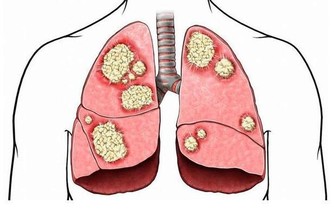

記得剛做住院醫生的時候,那時對卵巢癌患者做化療,

藥物中順鉑已是必備藥,而且現在這個藥還是卵巢癌化療的首選藥。

順鉑這個藥物對改善卵巢癌患者的預後起了很大的作用,

使80年代前的1年成活率不到20%,在使用這個藥後其2年成活率超過80%。

現在這個藥也用於其它惡性腫瘤的化療。

但這個藥有個很大的毒副作用,就是損傷腎臟,像氨基糖甙類抗生素一樣,引起腎小管壞死。